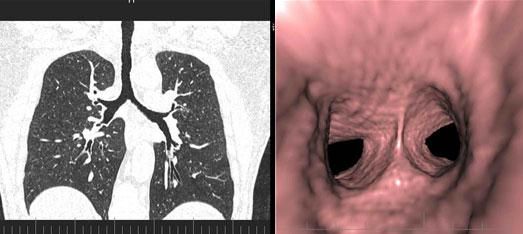

三、先進的仿真内鏡技術:

從多角度,多平面分析空腔髒器病變,可應用于胃、結腸、血管、氣管支氣管、膽道等仿真内鏡檢查,大大提高了病變的檢出率和診斷的準确性。